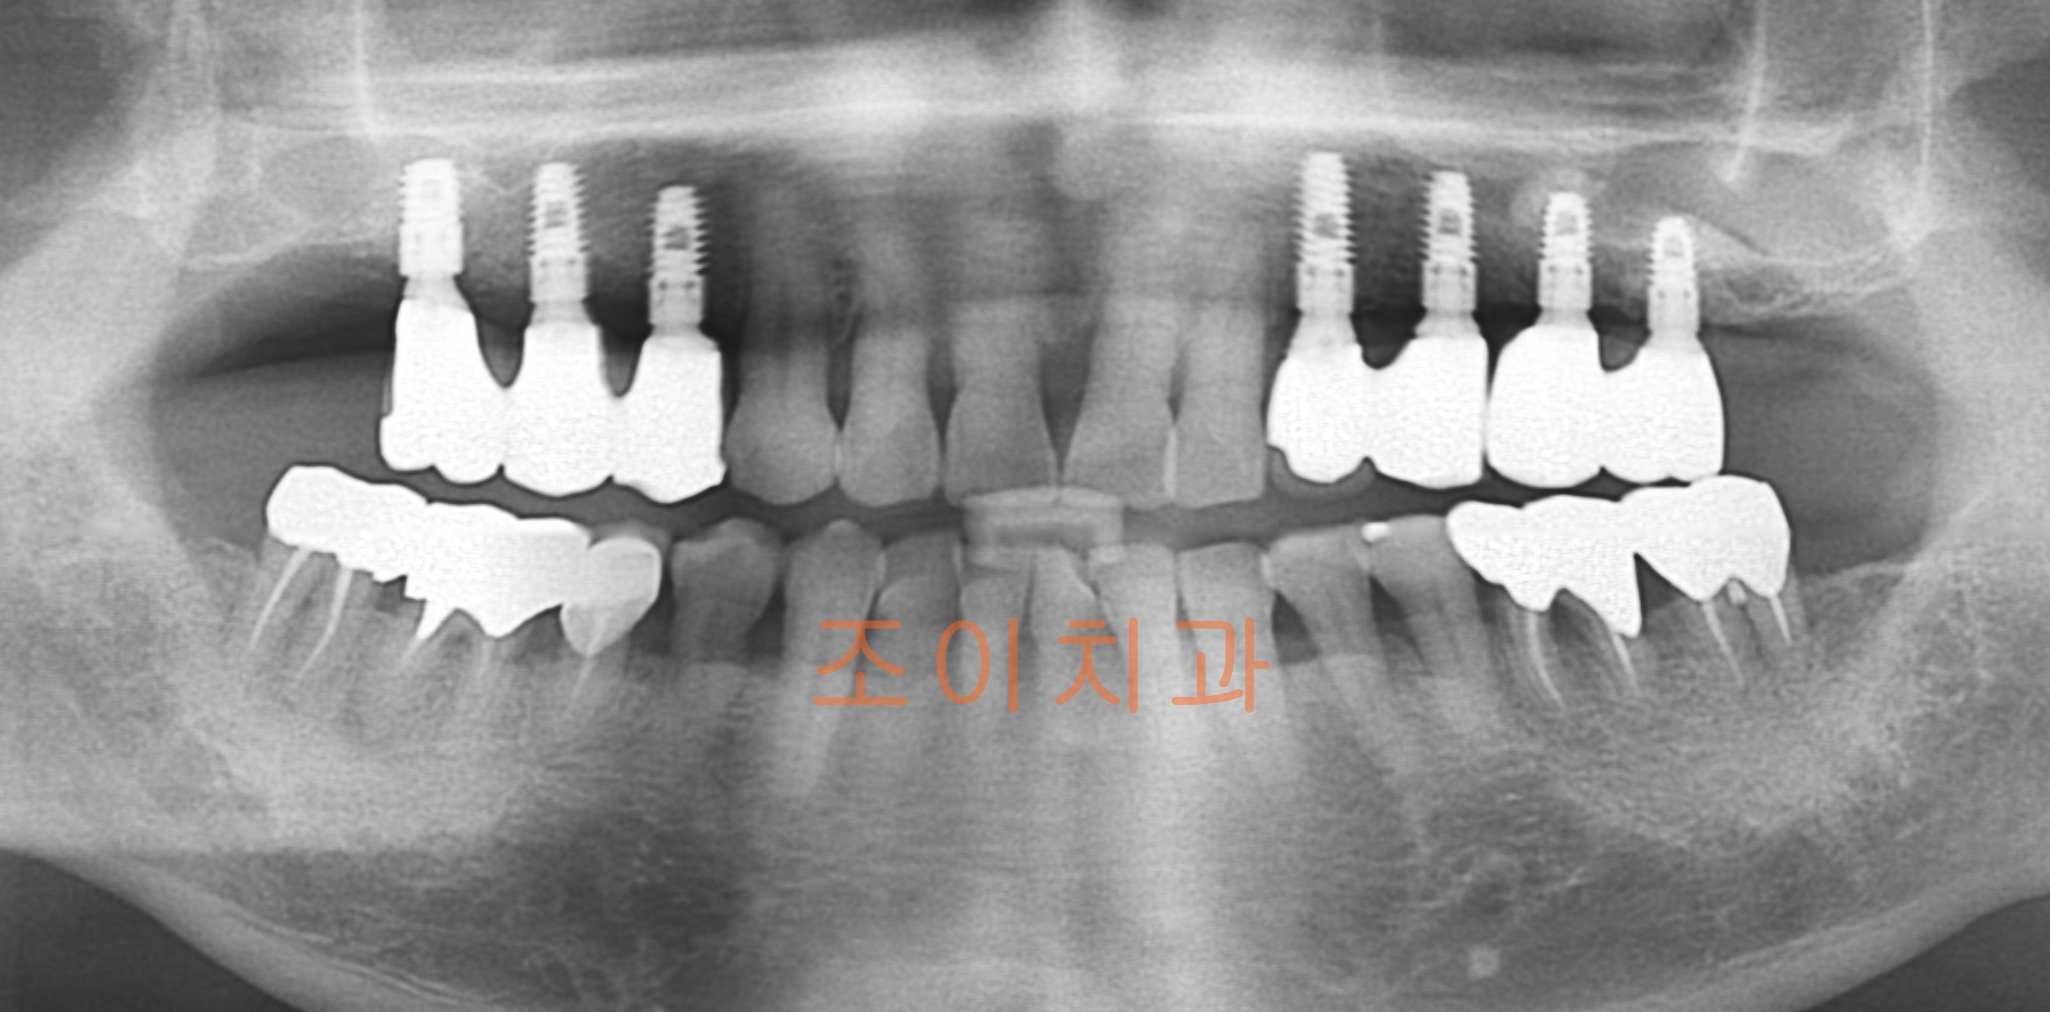

[임플란트] 제목 : 상악 임플란트

치주질환으로 인한 상악 임플란트 및 전반적 보철치료.